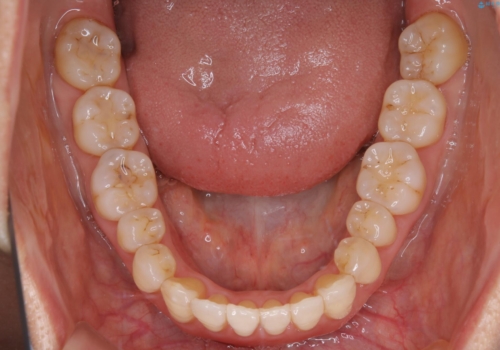

インビザラインによる非抜歯矯正を行いました。

IPRと呼ばれる、歯と歯の間を削る処置を行い、

がたつきを改善し歯を内側に入れることに成功しました。